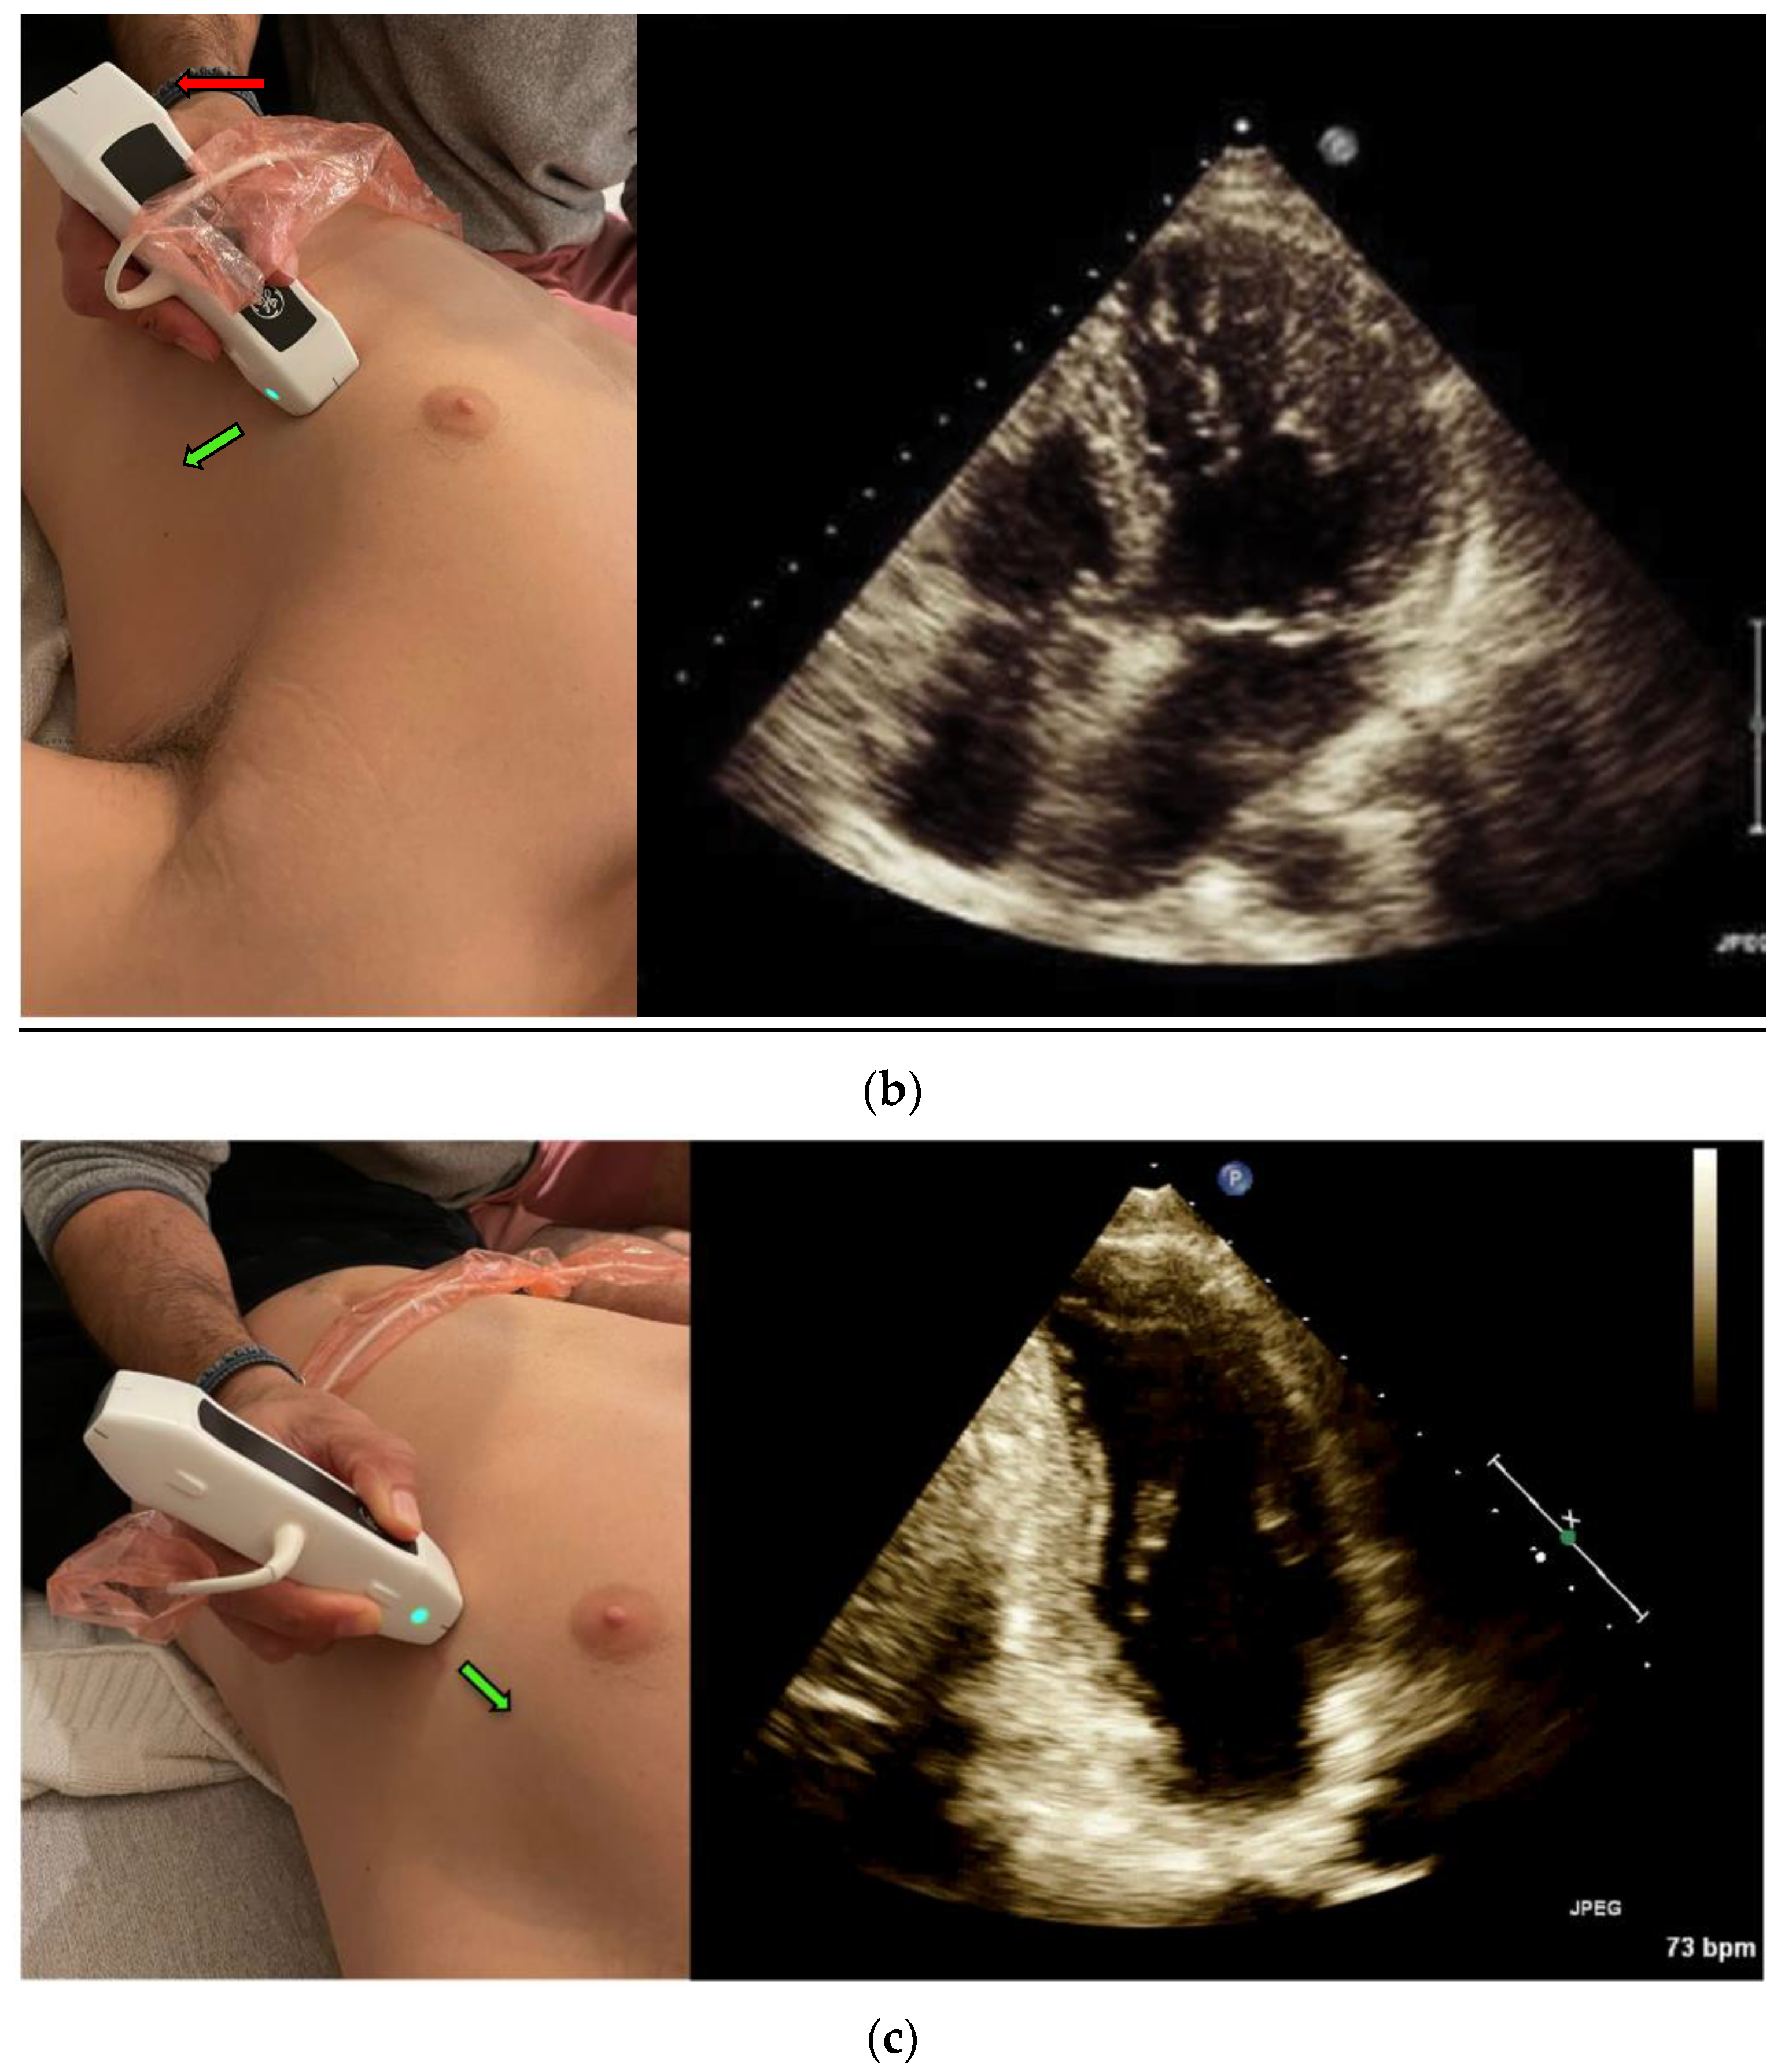

Once the User scans the A4CH view, the Real-Time EF tool identifies the view using Artificial Intelligence (AI) and Machine Learning (ML) algorithms. The semi-automatic tool traces the Ventricle walls per frame and identifies end diastolic and end systolic frames based on the maximal and minimal volumes measured in each heart cycle (Figure 2). Additionally, the tool calculates the image quality based on scanning quality, the tool’s identification of the A4CH view, and the consistency of the EF results. The quality indicator is reflected in the color of the contour. Additionally, if the A4CH view is not detected for more than a few seconds, the tool can indicate the expected location of the LV on the image to the User. Once the User freezes the image, the tool enables quick navigation between the acquired heart cycles and end diastolic and end systolic frames in the last 4 s. This allows for rapid review and selection of the preferable cycle to store and document.

Figure 2.

Auto EF tool: in Apical-4-Chamber-View: auto LV outlining in systole and diastole, measurements, and data display.

The auto LVEF tool provides two outputs—a score between 0–2 represented to the operator as a colored image quality marker (Red is poor = 0, Yellow is moderate = 1, Green is good = 2), and the EF assessment (presented as a percentage). The expert graded the views blindly, using the same score of 0–2 as the automatic tool for image quality (0—cannot comment on EF, 1—can estimate EF but endocardial border not fully demonstrated, 2—endocardial border well demonstrated), then estimated the EF by the eyeballing technique. We divided the LVEF expert’s assessment into three categories of LV function (preserved, mildly reduced, and reduced EF) as defined in the 2021 ESC Heart Failure guidelines for LVEF: (1) ≥50%, (2) 41–50%, and (3) ≤40%, respectively.